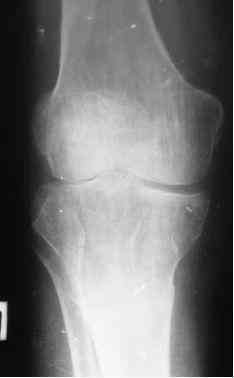

Анамнез: в 1992 г. оперирован в РНЦ «ВТО» по поводу ложного сустава шейки правого бедра (Р-снимок в приложении), 1994 перенес инсульт с исходом в правосторонний гемипарез. Передвигался без костылей, имея укорочение этой конечности на 3,5 см, порочную сгибательно-приводящую установку правого бедра и ДОА правого коленного сустава III ст. с перегрузкой латерального компартмента. Имеются дегенеративно-дистрофические изменения в поясничном отделе позвоночника. Больной до последнего времени «таксовал» на своей машине. 23 дня назад, поскользнувшись, упал в своей квартире, получил 2-х лодыжечном переломе костей правой голени с подвывихом стопы кнаружи (Р-граммы правового коленного и г/стопного суставов прилагаются). Помощь оказана в городском травмпункте г.Темиртау (Казахстан) Лечился гипсовой шиной, как рассказывает больной манипуляций на г/стопном суставе не проводили, посчитали, что все в порядке. Мое мнение - для создания опорной конечности необходимо произвести первичный артродез.Попов Виктор, г.Караганда.

легче чем восстановить.Если к ДОА коленного

сустава и тазобедренного сустава добавить

замкнутый голеностоп-вряд ли от этого биомеханика конечности выиграет.Три недели не такой уж большой срок чтобы отказаться от возможности открытой репозиции и МОС.

Показаний к артродезу в данной ситуации намного меньше, чем противопоказаний, связанных с поражением тазобедренного и коленного суставов.